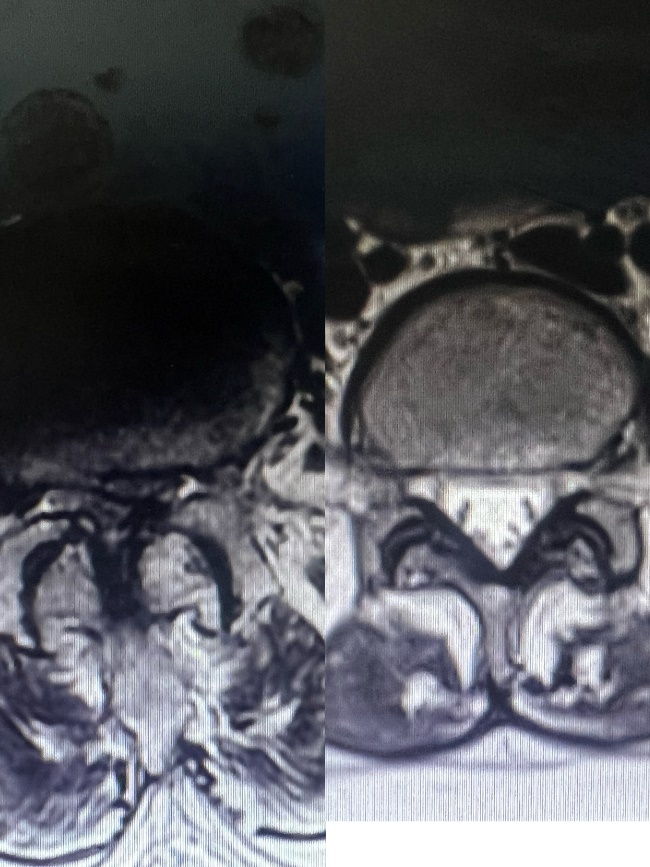

经检查发现,陈奶奶腰椎出现严重的多节段不稳伴神经管狭窄,在最严重区域,神经几乎被压成一条直线,情况十分糟糕!而且,陈奶奶还合并高血压、骨质疏松症等多种基础疾病,身体非常虚弱,这都大大增加了围手术期的风险。

▲与右侧正常腰椎椎管图比较,陈奶奶的腰椎椎管严重狭窄,

神经被压成一条直线